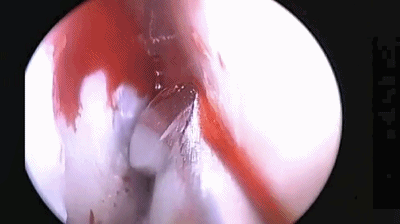

▼尖刀“X”划开鞍底硬膜

▼刮匙轻轻刮取肿瘤。

▼留取肿瘤标本。